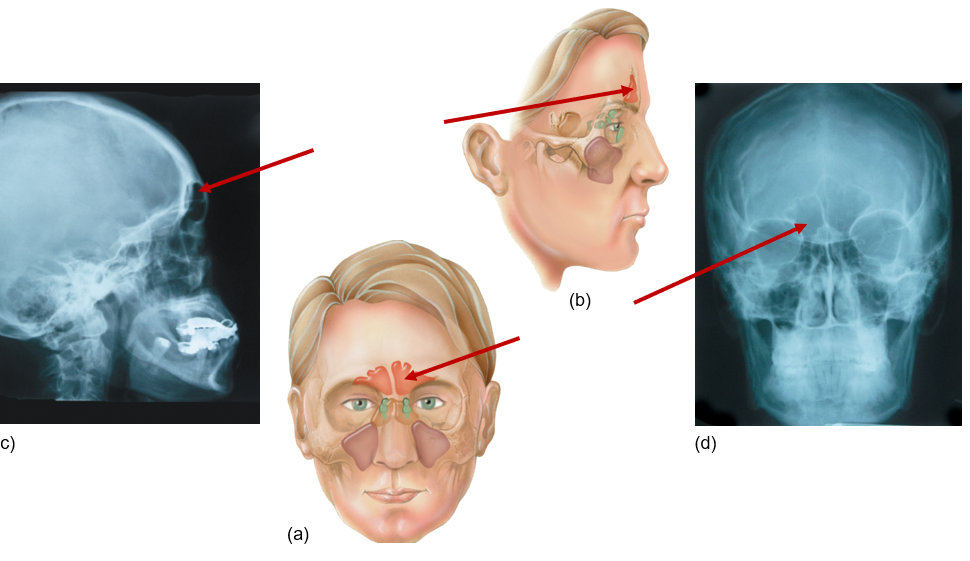

Frontal sinus

Front of head, above eyes

Sphenoid sinus

Behind eyes, near temples

Ethmoid sinus

Between eyes

Maxillary sinus

Next to nose, under eyes, maxilla